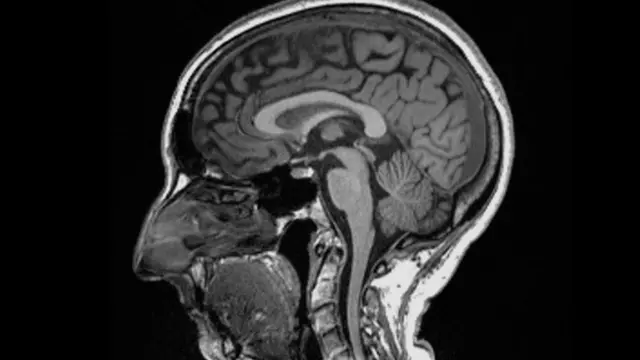

Être infecté par le covid-19 peut entraîner des changements dans le cerveau, selon une étude publiée dans la revue Nature.

Les chercheurs ont constaté des différences significatives dans les IRM réalisées avant et après l'infection.

Même après une infection légère, les images ont montré que la taille globale du cerveau avait légèrement diminué, avec moins de matière grise dans les régions liées à l'odorat et à la mémoire.